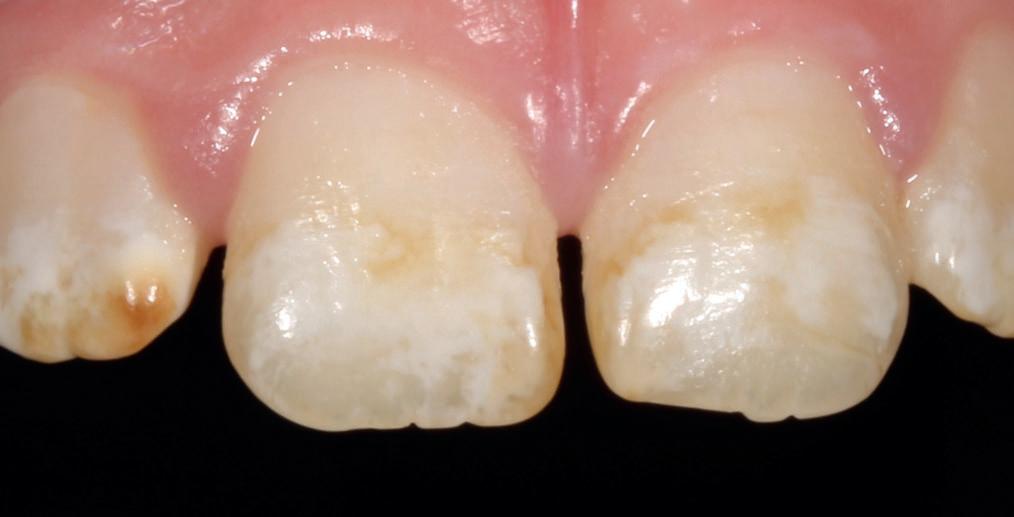

material matters

To use clear aligners to their greatest potential, it’s important to look briefly at their treatment ceiling. Complex cases that include severe bite issues, large gaps, or severe crowding may make this form of treatment less suitable, instead requiring traditional fixed braces. The literature has also cited distalisation, rotation and extrusion as some of the more difficult movements to carry out successfully with clear aligners, and whilst it is not impossible to achieve these results, a relevant case may prompt the need for an alternative treatment approach.

However, recent developments in the materials used to create clear aligners as well as clinical approaches have improved predictability in a wider range of cases.

Polyethylene terephthalate glycol (PETG) materials have been the solution of choice for many complex designs due to their durability, high impact strength and resistance to chemical changes. With impressive mechanical and optical properties, it’s easy to see why they are increasingly preferred.

The future of complex clear aligner cases could lie in shape memory polymers (SMPs), sometimes known as actively moving polymers. This material offers the ability to revert to an original shape when achieving a necessary transitionary trigger, such as a certain temperature for a designated time period. During a treatment cycle, the SMP-based aligner could be subjected to such a trigger, reverting to a predefined shape, and in turn generating forces which can produce orthodontic tooth movement. When designed to harbour multiple aligner shapes within its form, it could reduce the number of aligners used during orthodontic treatment and achieve complex corrections sooner.

Step by step

When tackling a complex case suitable for aligner therapy, treatment is most effective when the dentist creates an efficient and actionable treatment plan. Therefore, one of the most important skills for a clinician providing clear aligners for complex cases is an understanding of how to implement staging.

Those that have prior experience in orthodontics may know that staging refers to the breakdown of an intended movement of teeth in a sequential manner, with the use of aligners. This segmented approach

allows for the close control over linear and rotational movements over time, with each new aligner achieving a specific step that gets a patient closer to their end goal. In complex cases, staging orthodontic tooth movement is essential and can be used to attain better treatment outcomes.

When used in the treatment of severe crowding, staging has provided no significant differences in results when compared to fixed brace treatments, including in case duration. One 2022 study broke up the process into three overarching stages of ‘decrowding‘, ‘space closure’ and ‘fine-tuning’. This allows for targeted movement of the crowded anterior teeth, before achieving a class I canine and molar relationship, and making final adjustments, such as overcorrections – recommended by many in case of possible relapses – and closures of any residual spaces.